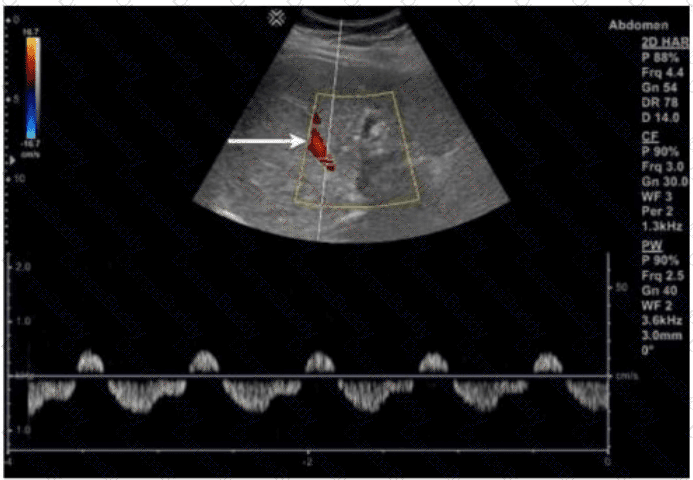

Which condition results in the vascular abnormality shown in this image of a renal transplant?